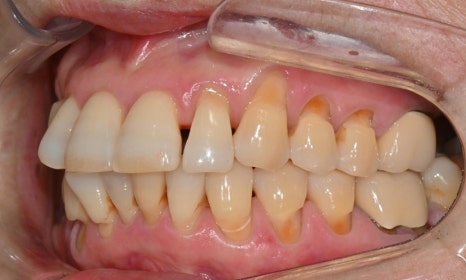

본 환자는 70세 여환으로 가만히 입을 다물고 있을 때 화난 것 처럼 보인다고 해서 튀어나온 앞니를 조금 넣고 싶다는 주소로 내원하셨습니다. 전체적인 치아 및 잇몸 상태를 검진해본 결과, 마모되어 깨진 치아도 있었고, 치경부(치아와 잇몸 사이 경계 부위)가 마모되어 파여 있는 부위도 많았습니다.

2025.2.3. 초진